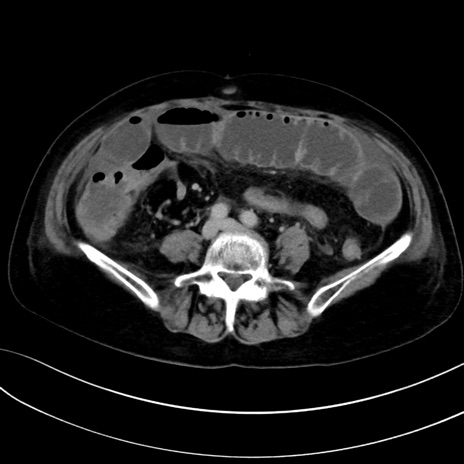

症例13 CT(横断像)1日半後